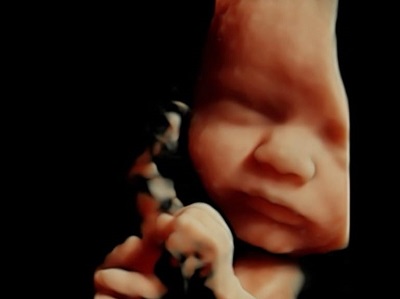

"Voir ce qui est invisible, grâce à des sons inaudibles."

En tant que profession médicale, nous pouvons pratiquer toutes les échographies de dépistage au cours de la grossesse, ainsi que les échographies pelviennes (gynécologiques), après l'obtention d'un diplôme inter-universitaire d'échographie obstétricale et gynécologique.

Nous réalisons les 3 échographies obstétricales recommandées pour le suivi de la grossesse.

échographie 3D